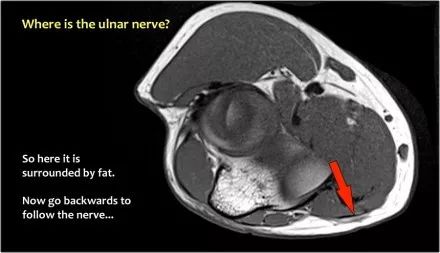

尺神经:在这里,我们看到了肘管内的尺神经。尺骨侧支带的后带形成隧道的底部,而支持带形成屋顶。

该患者有尺神经神经病变。肘管综合征是一种常见的周围神经病变。它产生于肘管内尺神经,其中该神经传递肘管支持带的下方的压缩。

因此,当我们回到图像时,您会发现很难找到神经。任何这些皮下结构都可以是转位神经。一种方法是远端跟随结构,直到你发现远端的尺神经位于由脂肪包围的前臂近端的正常位置。然后当你向近端跟随它时,你会发现这是皮下移位。